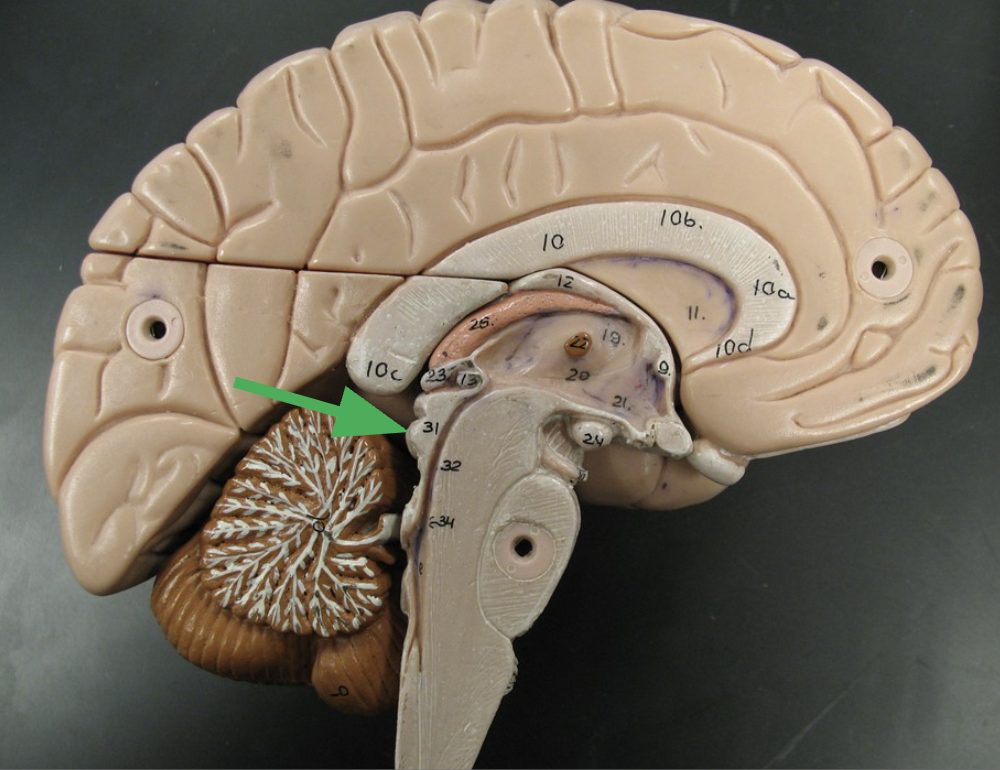

What section of the brainstem is this? What does it connect?

Pons “bridge”

connects diencephalon and cerebrum to the cerebellum and medulla oblongata

What does the pons do?

Nuclei involved in functions including chewing, swallowing, and breathing